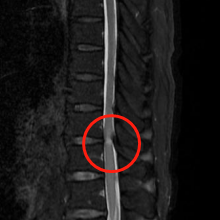

术前MRI影像提示胸椎黄韧带肥厚,胸段脊髓信号改变。

术前术后CT影像资料